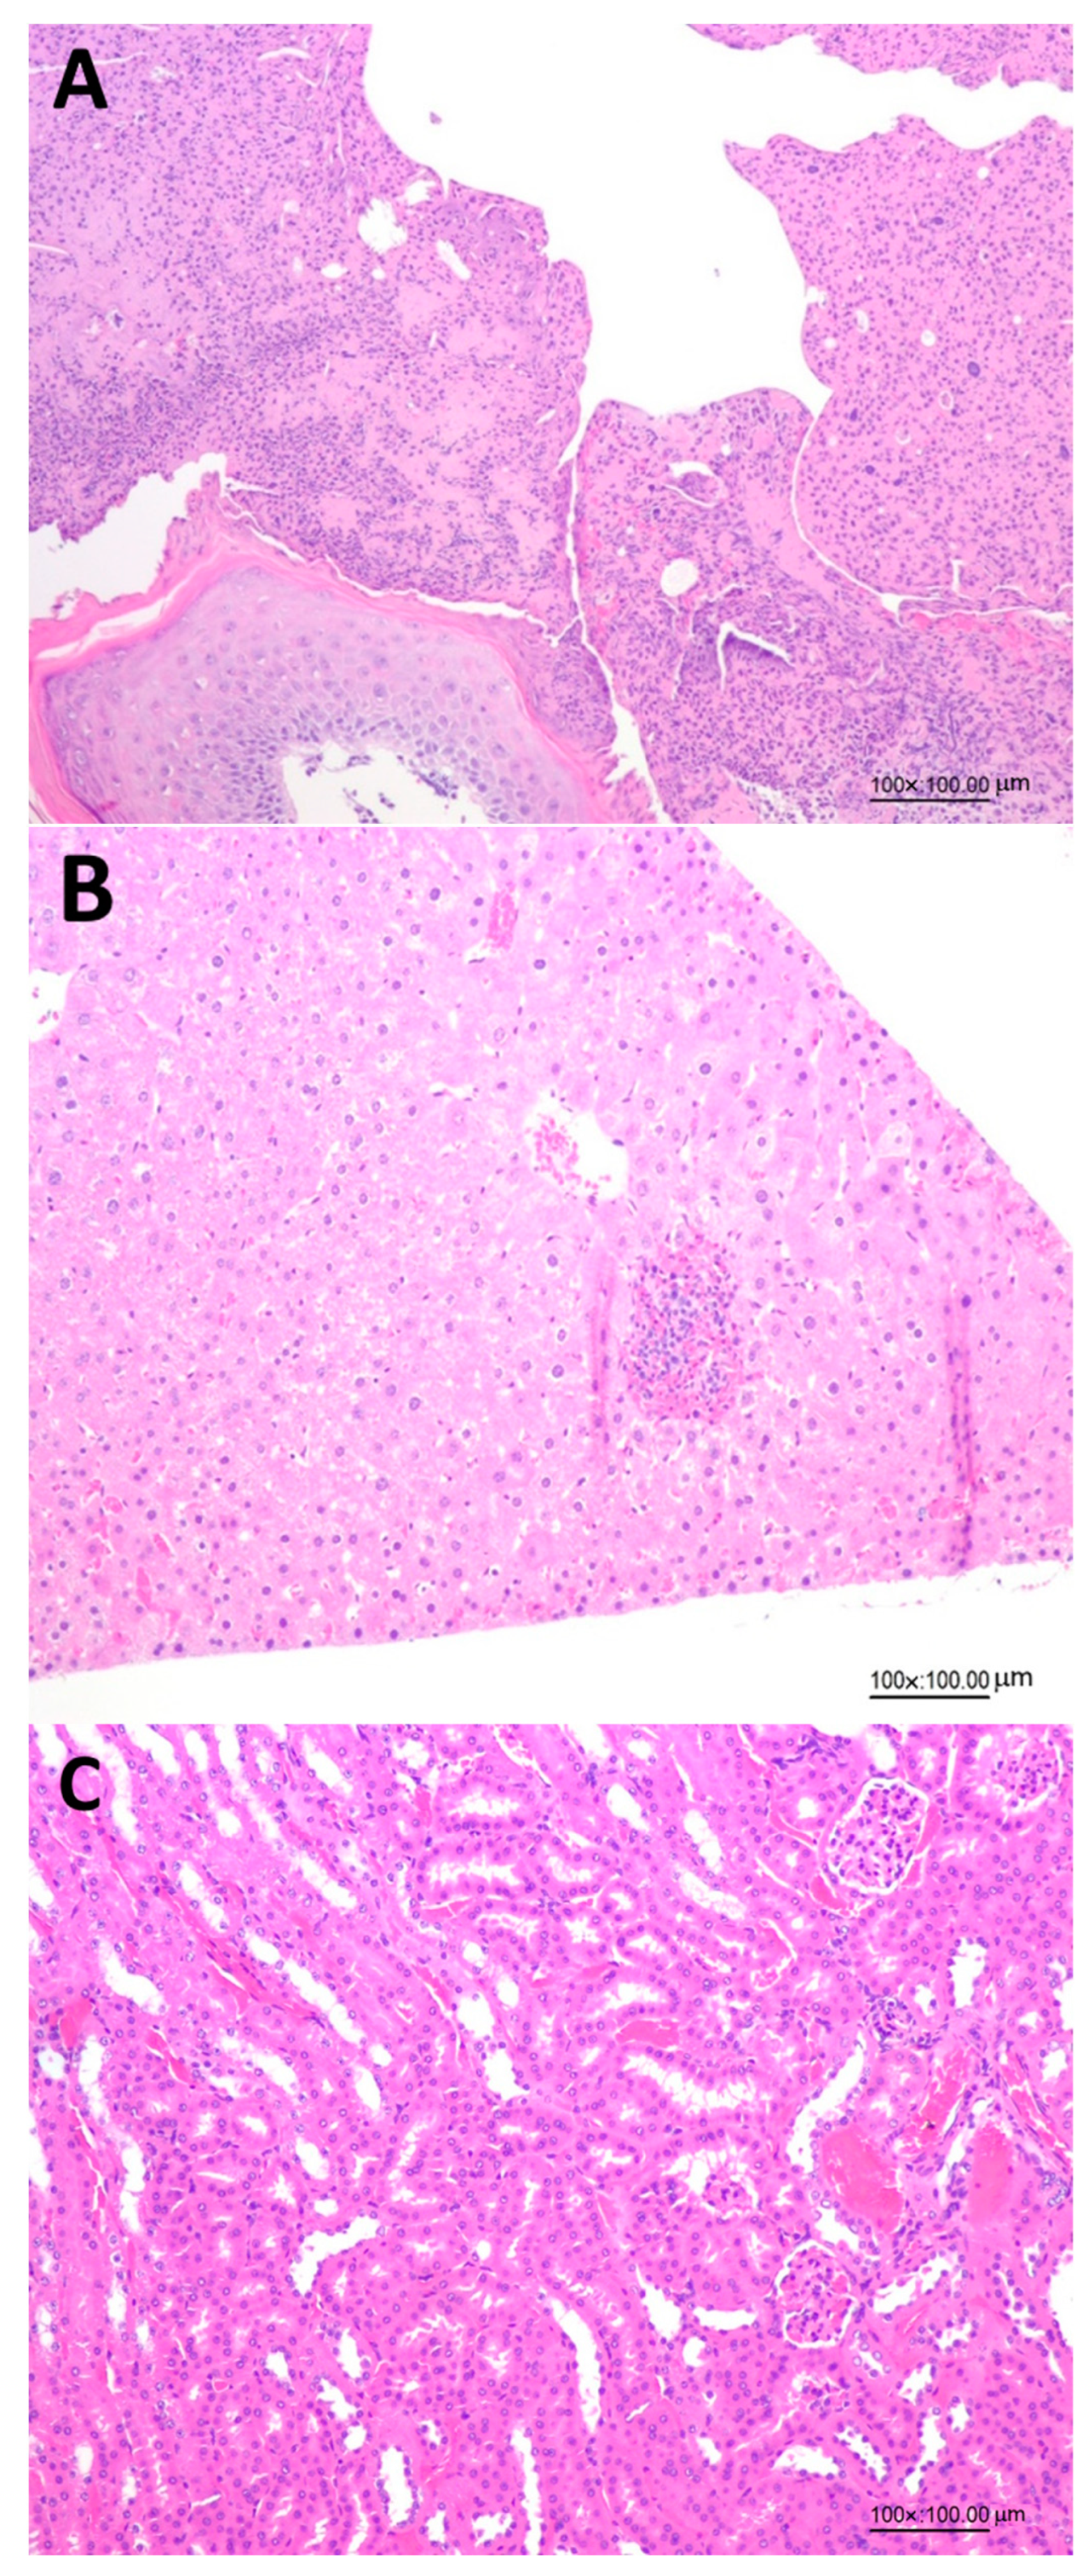

Figure 4 shows the effects of administration of LHN on the histopathology analysis of skin wounds, kidneys and livers in diabetic mice on day 15, demonstrating the safety of the collagen peptide nanoemulsion with low MW prepared in our study. This finding was further confirmed by histopathology of skin wounds (Figure 4A), livers (Figure 4B) and kidneys (Figure 4C) in diabetic mice on day 15 as affected by LHN.

Figure 4.

Effects of administration of collagen peptide nanoemulsion (LHN) on histopathology of skin wounds (A), livers (B) and kidneys (C) on day 15 in diabetic mice.